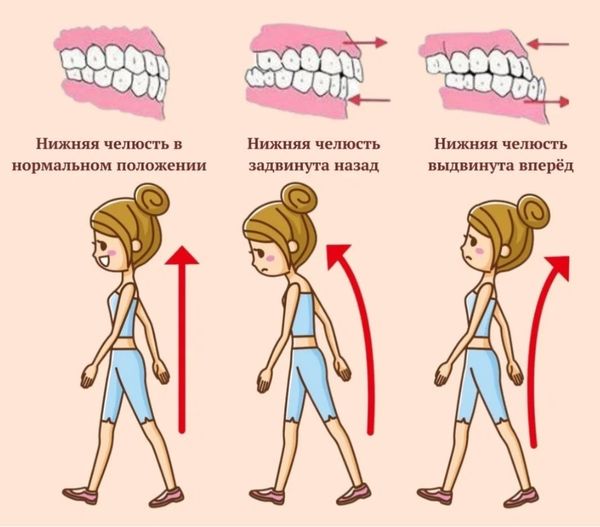

- Дистальный прикус (прогнатия) — патология прикуса, при которой нижняя челюсть меньше верхней или смещена кзади относительно верхней челюсти. У таких пациентов уменьшена нижняя треть лица, часто нарушена артикуляция, им тяжело откусывать и жевать пищу. Из-за дистального прикуса также может возникнуть дисфункция ВНЧС и стираемость зубов. При значительной стираемости передних зубов иногда теряются лицевые ориентиры, например опускаются уголки рта и углубляются носогубные складки [9]. Кроме этого, может развиться бруксизм (скрежет зубами), что тоже влияет на развитие асимметрии лица и челюсти.

- Мезиальный прикус (прогения) — нарушение прикуса, при котором нижняя челюсть выдвинута вперёд. Может возникать из-за раннего удаления зубов. При таком прикусе нижняя треть лица увеличена и может быть смещена в правую или левую сторону. При этом страдают жевательные мышцы и ВНЧС, так как головка мыщелкового отростка занимает неправильное положение. Таким образом запускается механизм развития асимметрии и нарушения функции всех структур лица.

Виды неправильного прикуса

6. Изменения в опорно-двигательном аппарате (изменение осанки, например сколиоз). Такие состояния могут влиять на развитие зубочелюстных аномалий. По данным некоторых авторов, нарушения прикуса и асимметрии у пациентов с заболеваниями опорно-двигательного аппарата встречаются в 1,6 раза чаще. Среди зубочелюстных аномалий на первом месте глубокий прикус, затем аномалии зубных рядов и дистальная окклюзия [4].

При неправильном положении костей скелета нагрузка на организм распределяется неравномерно, что влечёт за собой смещение костей и развитие аномалий челюстно-лицевого отдела. И наоборот, асимметрия челюсти может приводить к смещению центра тяжести, напряжению мышц шеи и далее к нарушениям в опорно-двигательном аппарате.

В Международной классификации болезней 10-го пересмотра (МКБ-10) асимметрия челюсти входит в раздел «Аномалии челюстно-черепных соотношений», к которому также относятся прогнатия (смещение вперёд) и ретрогнатия (смещение назад) нижней или верхней челюсти.